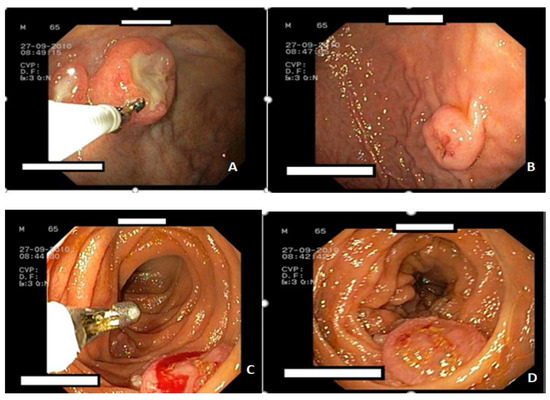

Metastatic melanoma is one of the most common malignancies associated with the spread of the primary tumor. The primary site is usually the skin or the eyes. The most frequent site of metastases is the gastrointestinal tract, accounting for 60% of cases at [...] Read more.

Metastatic melanoma is one of the most common malignancies associated with the spread of the primary tumor. The primary site is usually the skin or the eyes. The most frequent site of metastases is the gastrointestinal tract, accounting for 60% of cases at autopsy. In 2% of patients, metastases occur without a detectable primary tumor. We present a rare case of upper digestive bleeding caused by multiple gastrointestinal tract metastases from an amelanotic melanoma. This case report describes a 65-year-old male who arrived at the emergency department after experiencing an episode of upper gastrointestinal bleeding (melena). One week prior to admission, he had been treated with nonsteroidal anti-inflammatory drugs for lower back pain due to L4–L5 disc herniation. Upper digestive endoscopy revealed multiple polypoid masses in the stomach and duodenum, and capsule endoscopy showed additional lesions in the small bowel. Histopathological examination confirmed the diagnosis: metastases from an amelanotic malignant melanoma. Abdominal and cranial computed tomography scans revealed multiple secondary lesions in the brain, gallbladder, retroperitoneal area, gastrointestinal tract, and peritoneum. Localized radiotherapy was applied to the cerebral metastasis, and systemic chemotherapy with dacarbazine was initiated, resulting in a partial clinical response. Unfortunately, the disease progressed, and the patient died one month after diagnosis. Metastatic melanoma of the gastrointestinal tract is an exceedingly rare cause of upper digestive bleeding. Full article